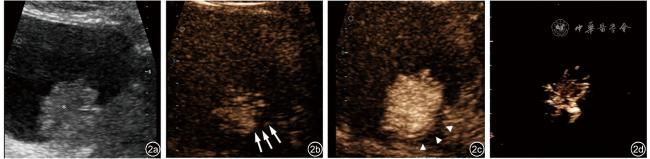

图2 一例66岁男性非肌层浸润性膀胱癌患者常规超声及高帧频超声造影图像。图a:常规超声可见膀胱壁上一低回声病灶(*);图b:来自黏膜层微泡进入病灶(↑);图c:动脉期显示完整的固有肌层(▲);图d:病灶内部不规则血管影

在H-CEUS观察下病灶的基底宽度、血管支数、微泡直接进入病灶的膀胱壁来源层面以及固有肌层的完整性方面,MIBC组与NMIBC组的差异均具有统计学意义(P均<0.05,表2图12)。MIBC组的基底较NMIBC组宽;MIBC组的血管分支数目多为≥3支(57.1%,4/7),而NMIBC组多为1~2支(68.7%,11/16);与MIBC组相比,NMIBC病灶基底处微泡多仅从黏膜层进入病灶(75.0% vs 14.3%),MIBC组的固有肌层均不完整(100% vs 18.7%)。NMIBC组与MIBC组在病灶平行径、垂直径、垂直径与平行径比值、血管形态方面比较,差异均无统计学意义(P均>0.05,表2)。